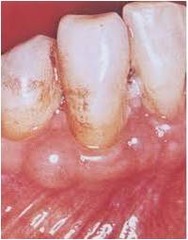

Type of cyst: found in salivary glands; elevated, translucent, bluish; mucous containing

Front

Mucocele (similar to Ranula, except Ranula is a salivary gland disease that is severe blockage of the duct)